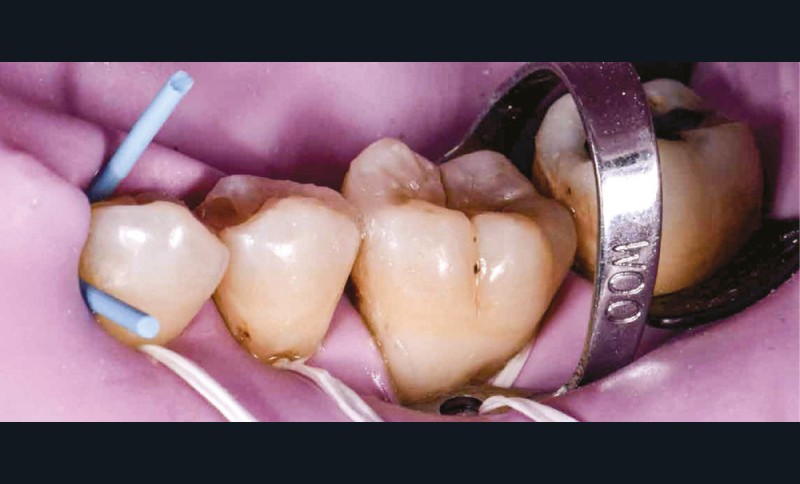

La première anesthésie se situe au niveau de la papille proximale entre 35 et 36. L’aiguille blanche de diamètre 0,30 mm et de longueur 16 mm est orientée de façon à avoir son repère légèrement décalé de la fenêtre du porte-aiguille (fig. 4). Ainsi, le biseau se pose à plat contre la muqueuse [1]. L’aiguille glisse doucement et de façon indolore dans la papille sur 2 mm et l’injection débute sans surpression sous contrôle électronique. Lorsque la papille montre une vasoconstriction suffisante, elle devient blanche et l’injection peut s’arrêter. La pièce à main s’oriente alors en direction de l’espace apical interdentaire avec un angle de 30 à 45° vestibulolingual (fig. 5). L’aiguille est mise en rotation pour pénétrer la corticale osseuse. Elle arrive ensuite dans la partie trabéculaire de l’os. Lorsque les deux tiers de l’aiguille sont sous la corticale, la rotation doit cesser et l’injection reprend avec une vitesse qui s’adapte électroniquement à la densité de l’os. Une demi-carpule d’articaïne 1/100 000 suffira à la restauration de ce secteur [2]. Le champ opératoire, le crampon, les ligatures sont placés (fig. 6) ; un crampon additionnel permet de descendre la ligature dans le sulcus de la 36 pour réaliser le soin vestibulaire (fig. 7). Les restaurations sont réalisées sans douleur (fig. 8) [3].